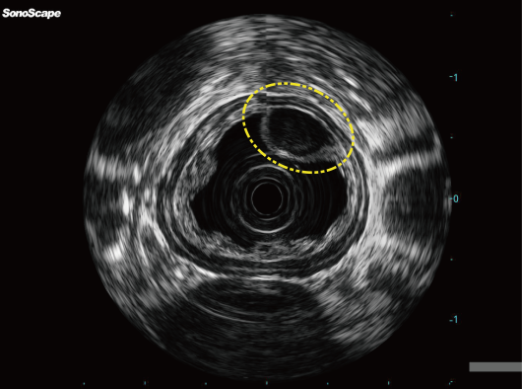

30836a0c45f36bfa78d0262156d5e61c.png

195bf9db8d1435c8e97db89b1c379104.png

图:食管上皮下病变-食管平滑肌瘤